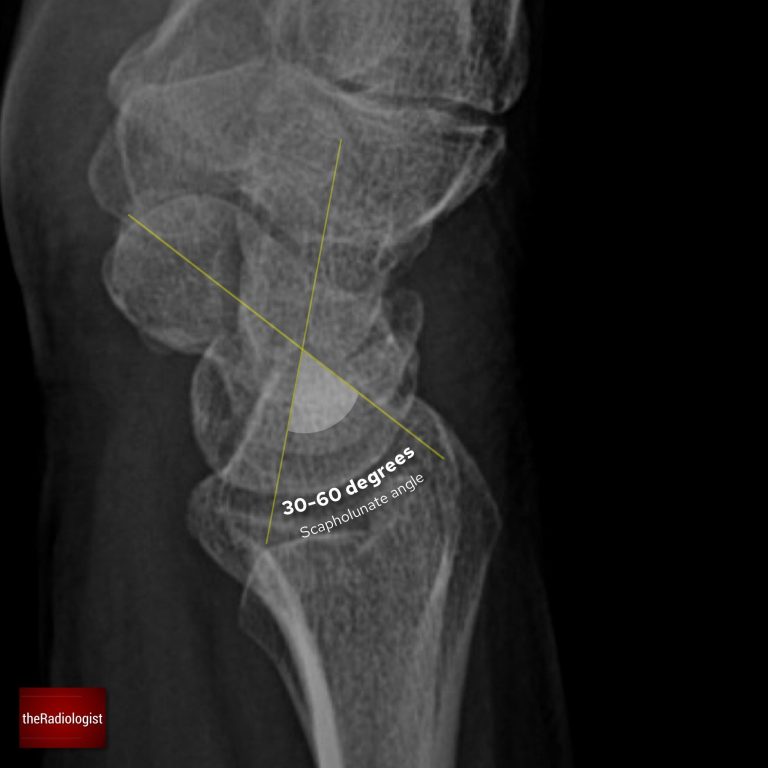

Scapholunate angle

On a well-positioned true lateral wrist X-ray, one of the most informative measurements you can make is the scapholunate (SL) angle. It reflects the alignment between the scaphoid and lunate. When their relationship breaks down, instability patterns emerge that can progress to long-term arthritis if missed.

You can measure it by drawing a line along the long axis of the scaphoid and drawing another line along the long axis of the lunate. The angle between these two lines is the scapholunate angle.

Normal range: 30–60°.

>70–80° suggests DISI (Dorsal Intercalated Segment Instability) whilst <30° suggests VISI (Volar Intercalated Segment Instability).

A normal scapholunate angle ranges between 30-60°. An increase suggests DISI whilst a reduction suggests VISI.